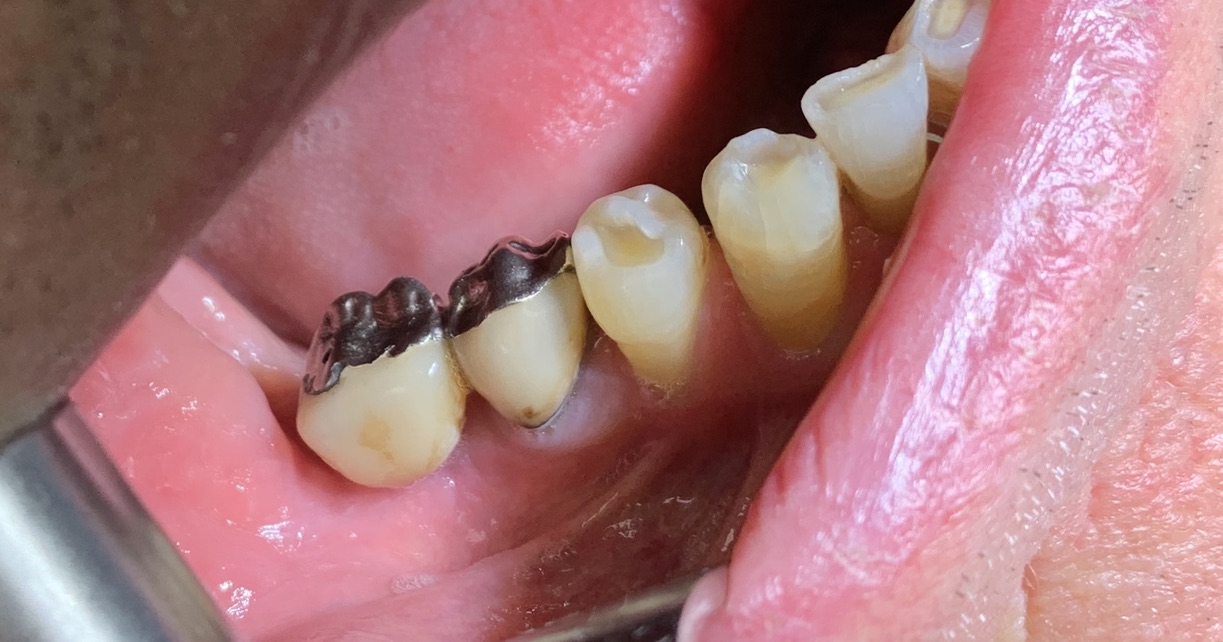

1 - UN CASO INCISIVO

Frattura di elemento incisivo inferiore 31 e riabilitazione implantare